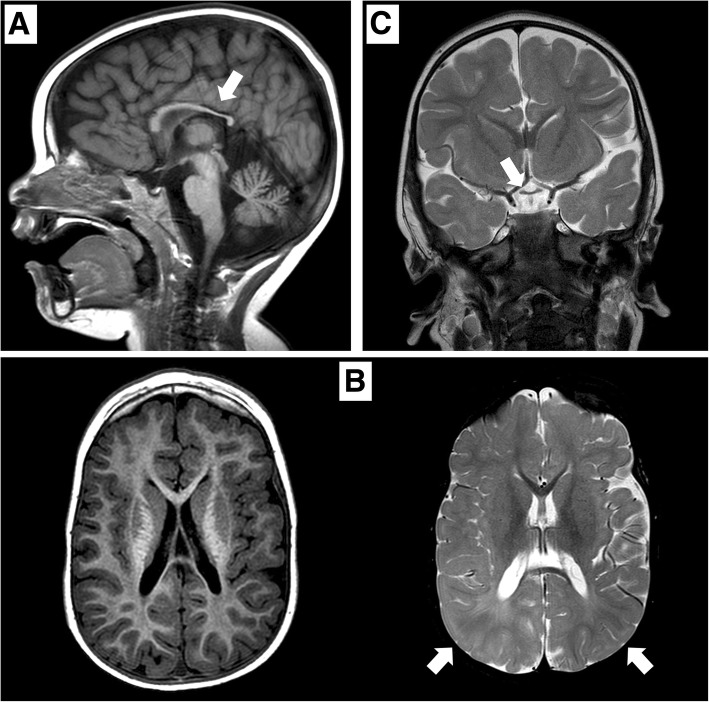

矢状位 T1 加权图像显示胼胝体发育不全(白色箭头)。 b 轴向 T1 加权(左)和轴向 T2 加权(右)图像显示胼胝体发育不全和双侧皮层下顶叶白质(白色箭头)中改变的、不明确的信号。 c 显示视交叉发育不全的冠状 T2 加权图像(白色箭头)

根据《人的基因序列变化与人体疾病表征》,过去有部分机构和医务人员认为德莫塞尔综合征不是遗传性疾病,甚至有人认为该病不是由基因引起的,德莫塞尔综合征发生的内在基因原因被忽视。佳学基因通过基因解码找到并定位了导致这一疾病发生的原因,提出了德莫塞尔综合征的遗传风险,并建议通过基因检测明确和排除风险,让后代、二胎不再患有德莫塞尔综合征,实现德莫塞尔综合征遗传阻断的目的。佳学基因病案集中一个患者是一名 2015 年出生的男孩,是健康父母的第二个孩子。 他有一个健康的姐姐,姐姐于 2011 年出生。他出生时妊娠 376/7 周,顺产(体重,2.4kg;z-分数,->1,65;长度,45-cm;z-分数, − 2.45;头围,31 cm;z 分数,- 1.84;Apgar 评分,1 分钟 8 分和 5〉 分钟 8 分)。 出生后 5 小时,他因低血糖(床旁检查,29mg/dl)被送入新生儿病房,并接受了 72 小时的静脉葡萄糖输注。 先天性巨细胞病毒感染的脑超声和实验室检查结果均正常。6个月大时的初步评估显示整体发育迟缓。 患者的体格、营养和身高对于他的年龄而言是正常的(z 评分,+ 0.64)。 检查显示小头畸形(z 评分,− 1.56)、畸形特征(薄上唇、尖腭、低植发、长人中、广泛的睑裂)、肢体异常(右脚趾和双脚足底垫植入异常) )、小阴茎和隐睾。患者出现全身性肌张力减退; 他无法实现头部控制,并表现出水平眼球震颤、眼球运动障碍和视力障碍。 没有癫痫发作史。 头颅磁共振成像 (MRI) 显示髓鞘形成延迟、胼胝体发育不全(图 1)和垂体发育不全。 没有闪光视觉诱发电位反应。

在 2 岁时,患者无法保持目光接触,也没有发展语言技能。 直到 3 岁时,他才能独立坐下。此时,头颅 MRI 显示双侧视神经发育不全,并证实胼胝体发育不全(图 (图 1).1)。 为评估先天性心脏缺陷而进行的超声心动图显示无阻塞的室间隔肥大。